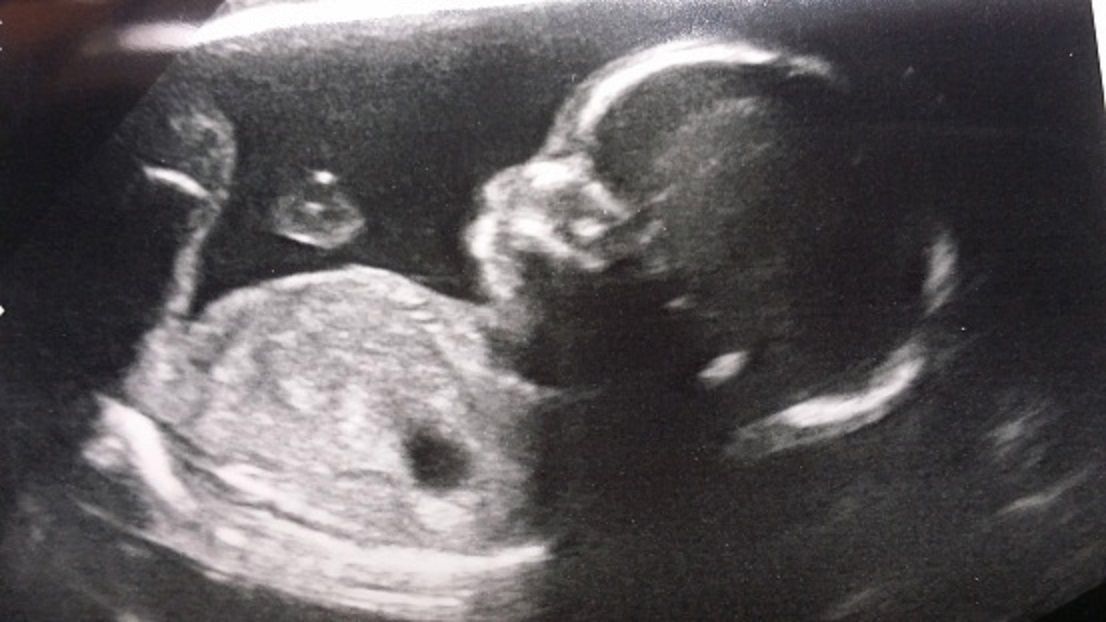

Terapia Bowena pomocna w odwróceniu niewłaściwie ułożonego płodu

Jednym z zastosowań Terapii Bowena jest możliwość odwrócenia dziecka, które ułożyło się pod koniec ciąży w niewłaściwej pozycji. Jak to się dzieje?

Za pomocą delikatnych ruchów na miękkich tkankach (przeponie, mięśniach pleców, krzyża, miednicy) powodujemy nawilżenie powięzi, zwiększamy elastyczność wszystkich dotkniętych i połączonych z nimi struktur mięśniowych i powięziowych i w ten pośredni sposób wpływamy na bardzo głębokie tkanki.

W efekcie tego działania przestrzeń dziecka staje się przestronna i miękka, dzięki czemu może ono poruszać się nieco swobodniej. Ponieważ głowa dziecka pod koniec ciąży jest już dużo cięższa niż reszta ciała, po uzyskaniu większej swobody maluch, w czasie swoich naturalnych ruchów ląduje głową na dół i w tym ułożeniu już pozostaje aż do porodu.